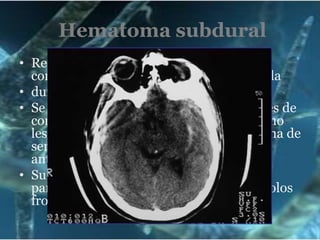

Hematoma subduralResultado de la ruptura de venas comunicantes entre la corteza cerebral y laduramadre, Se localiza con más frecuencia en regiones de contragolpe, observándose en la TAC como lesiones hiperdensasyuxtaóseascon forma de semiluna y bordes menos nítidos que el anterior. Su localización más frecuente es en zona parietal, respetando habitualmente los polos frontal y occipital.

Hematoma subduralLa acumulación de la sangre debajo de la duramadre es de origen venoso por ello da mas tiempo para su tratamiento.Este tiempo esta en dependencia de la atrofia cortical que el anciano presente, ya que la sangre acumulada en este sitio puede no dar signos, lo mas común es de 6 hrs en adelante.Grave ya que pone en peligro la vida del adulto mayor.Resolución final es quirúrgica.